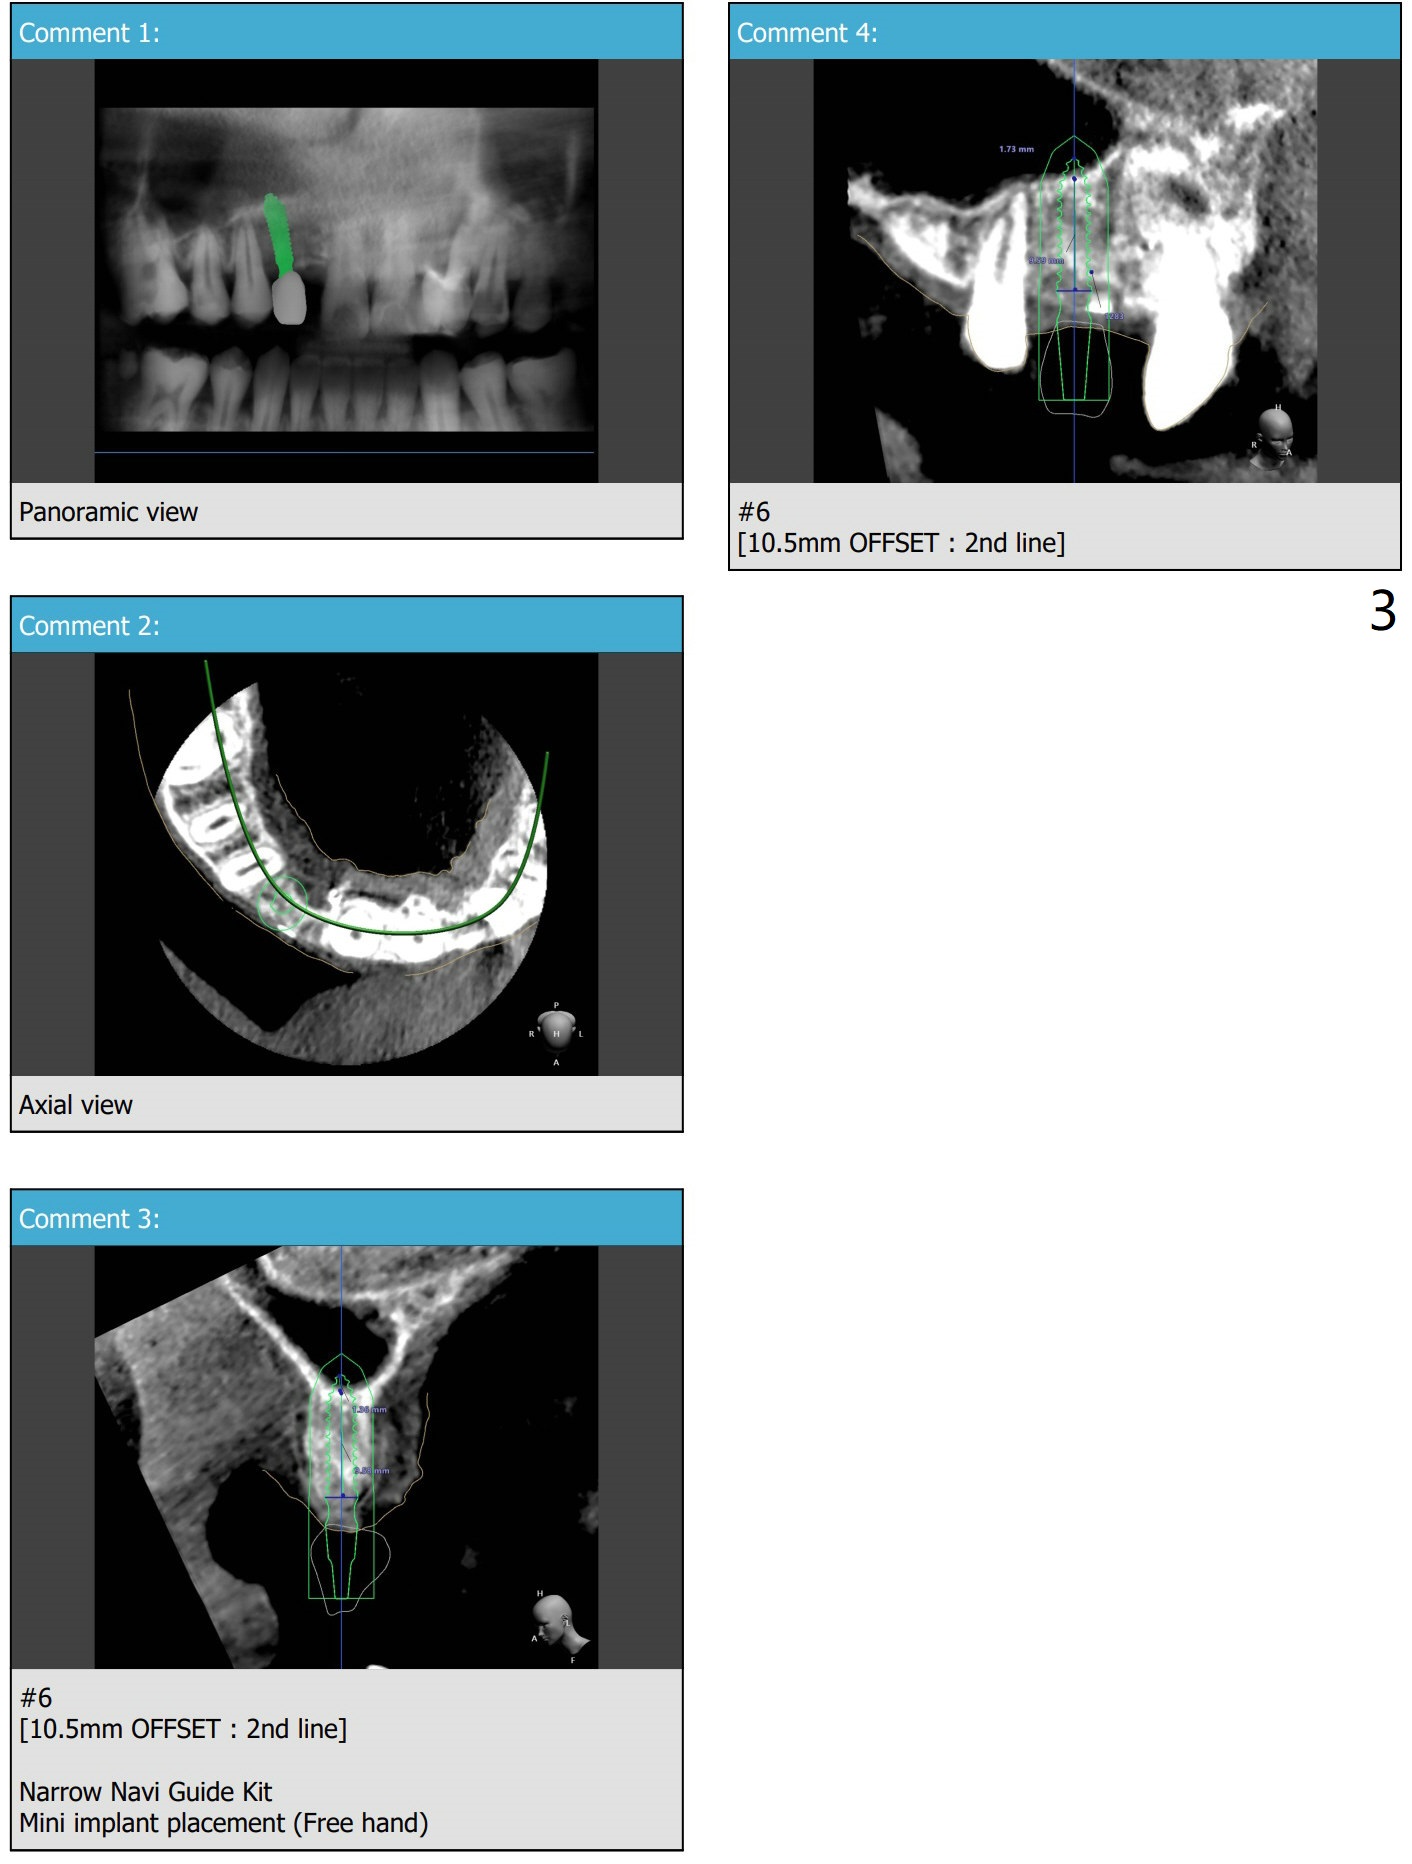

第二次植入

6号牙植体取出植骨5.5月,需要切开去除带钛不可吸收膜和两个固定钉,抽血一管